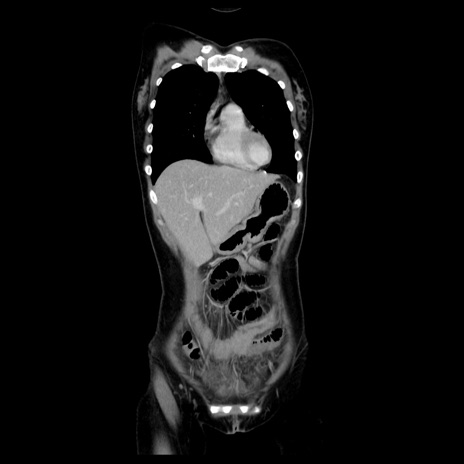

MRI(4日後)